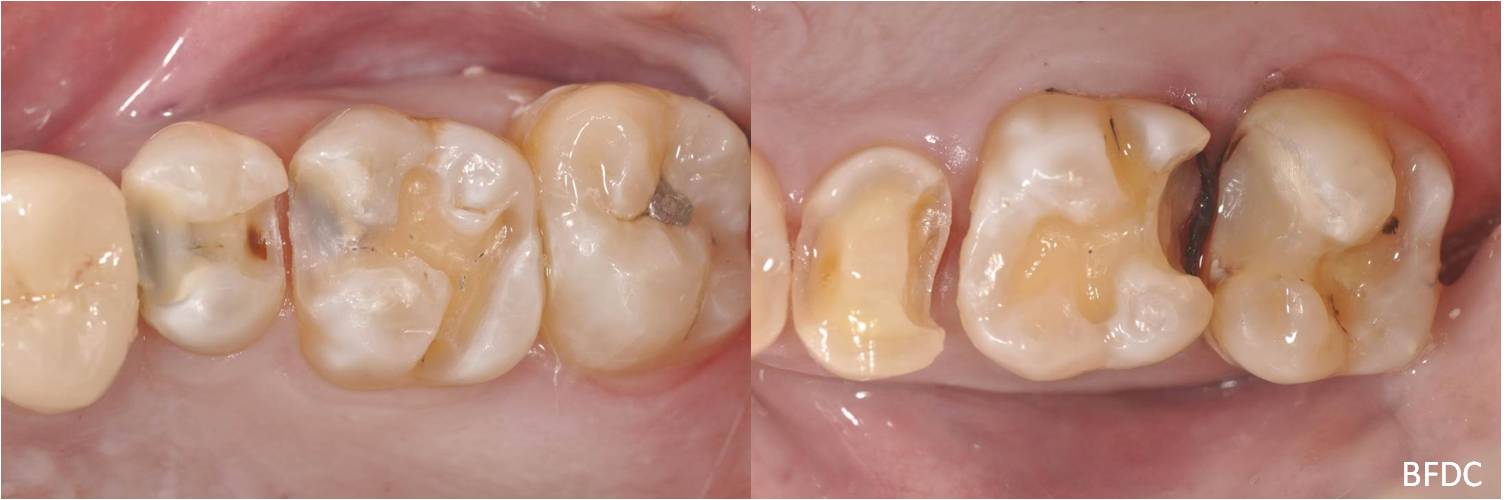

陶瓷崁體及冠蓋體-蛀牙-#1516172526 大範圍的補皮,該如何選擇,嵌體的方式就適用於大範圍的填補,因為它是一體成形, 嵌體材質多種,以往才會使用黃金合金,但因價格昂貴且顏色太過突出,因此現在多使用玻璃陶瓷二氧化鋯等材質的全瓷冠。嵌體有其優勢,因一體成形的材料,硬度和穩定性都較高,不用一點一點填補,減少下方凹陷重複蛀牙的危機,也不會變形或染色,美觀度高很多。 #1516172526蛀牙 #1516172526蛀牙 崁體及冠蓋體修形 安裝模型至咬合器 嵌體及冠塊體製作 陶瓷崁體及冠蓋體 黏著後 黏著後X光 術前、術後比較 嵌體有其優勢,因一體成形的材料,硬度和穩定性都較高,不用一點一點填補,減少下方凹陷重複蛀牙的危機,也不會變形或染色,美觀度高很多。

能避免片狀樹脂造成的,下方重複蛀牙,或彈性大造成咬合不舒服的問題,若有多顆牙齒填補,或坑陷較大者,如牙齒已蛀超過1/2或2/3者,才建議使用此種方式。